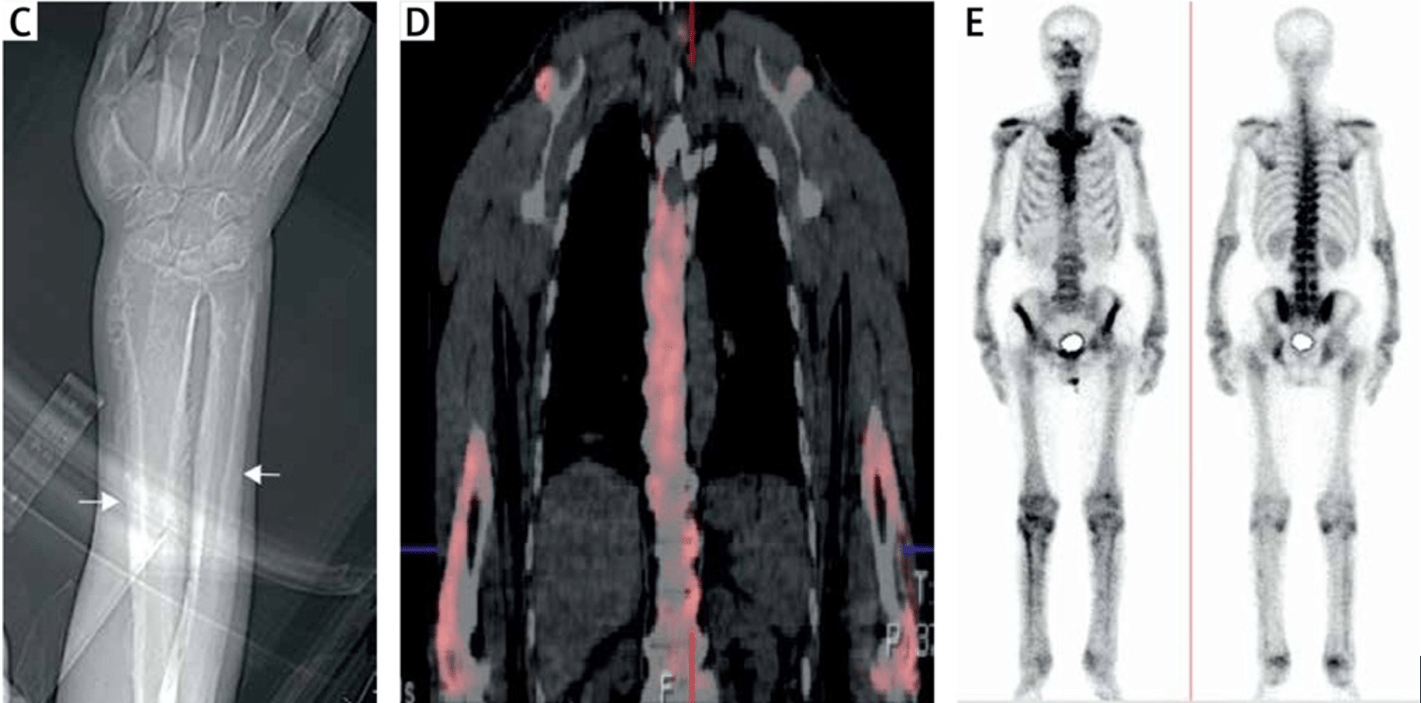

This paraneoplastic syndrome most commonly associated with lung adenocarcinoma is characterized by painful swollen joints and digital clubbing

What is hypertrophic (pulmonary) osteoarthropathy?

Digital clubbing, increased periosteal activity of the tubular bones, arthralgias, and joint effusion. Lung adenocarcinoma accounts for 90% cases.